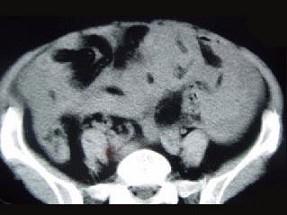

问题 50岁女性患者,消瘦乏力一年余,来院就诊,B超提示盆腔巨大包块,行CT检查如图所示,你认为最可能的答案是 ( )

选项 A、卵巢粘液瘤 B、卵巢皮样囊肿 C、卵巢囊肿 D、卵巢异位妊娠 E、卵巢癌

答案 E